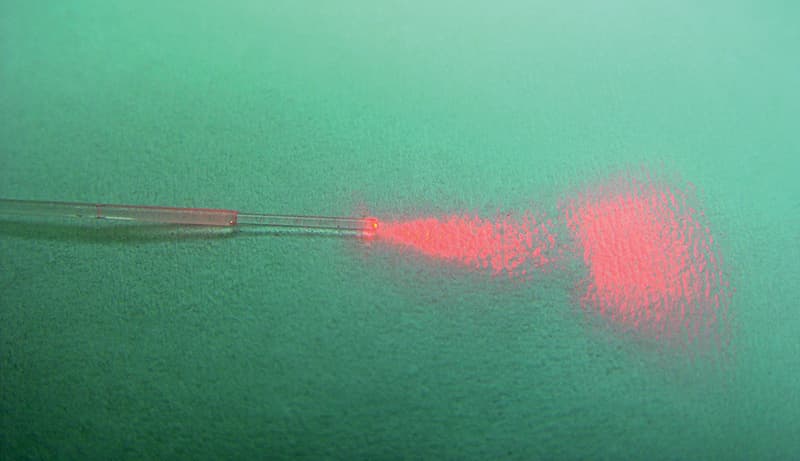

LA THERMO-OBLITÉRATION PAR LASER

utilise une sonde laser introduite dans le tronc saphène par ponction sous le genou.

Des flashs de lumière laser sont appliqués tout au long du tronc veineux. La brûlure interne de la veine aboutit à son oblitération. C’est une technique qui n’est aussi réalisable que dans certaines conditions anatomiques. Cette procédure est plus simple et plus rapide mais aussi techniquement moins contrôlée. Elle est souvent assez douloureuse sur son trajet au niveau de la cuisse, surtout à partir du 3e ou 4e jour et dure parfois plus d’une semaine. Cela nécessite souvent la prise d’anti-inflammatoire.